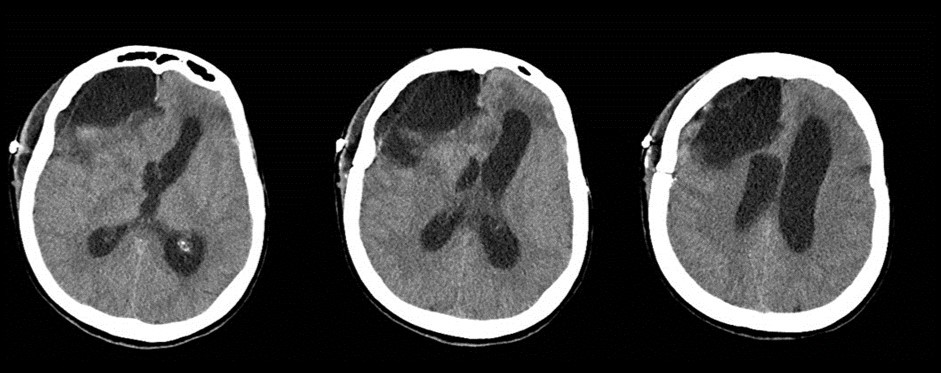

Figure 2.Follow-up at 6 weeks. The vascular clip is in place. Ventricles are quite enlarged. The region of the corpus callosum appears altered

The follow-up CT scan made two weeks later showed a mild ventricular enlargement and persistent density alterations in the frontal region (Figure 2) that were interpreted as normal. Once discharged at home, the patient developed progressive disorientation that finally let her refer to our hospital for consult four months after aneurysm clipping. The cerebral CT we performed showed further ventricular growth, and a tumor-like image in the right frontal lobe (Figure 3). She was admitted to our ward and underwent a contrast-MRI that confirmed the suspicion of aggressive intra-axial neoplasm (Figure 4). The week after, under general anesthesia we performed a right craniotomy and removed a large part of the tumor, sparing the portion going through the corpus callosum (Figure 5). During convalescence the patient had few epileptic attacks, treated with drugs. A mild cognitive impairment persisted after surgery, without focal motor deficits. The gait, limited and unstable since the SAH, remained poor and the patient never walked again after the operation. The histological examination indicated a WHO grade IV glioma: IDH1-p53 negative glioblastoma. The patient and her relatives refused a ventriculo-peritoneal shunt after knowing this unfortunate diagnosis. Transferred to rehabilitation, the woman made just a short low-dose chemotherapy cycle and finally died four months after tumor resection.

The clinical and radiological features of these two diseases are perfectly known to neurosurgeons; anyhow our case shows that trouble rises when they do occur simultaneously. The patient we described had initially acute signs due to SAH and later signs that were incorrectly interpreted as SAH-related. The tumor was almost invisible -because of its likely small volume and thick SAH- in the first CT performed (Figure 1). Analyzing the early follow-up CT (Figure 2) anyway things do not seem so clear. In the frontal region remained too much fogging close to the midline; the asymmetric distribution of such alteration should had point out a problem, but everybody kept thinking to a “simple” post-hemorrhagic condition, due to ventricular enlargement and focal ischemia. The initial mental impairment of that period was equally attributed to a normal SAH result with moderate hydrocephalus. The proper diagnosis of glioma happened late, and the patient was at that point unable to have significant benefits from surgery.